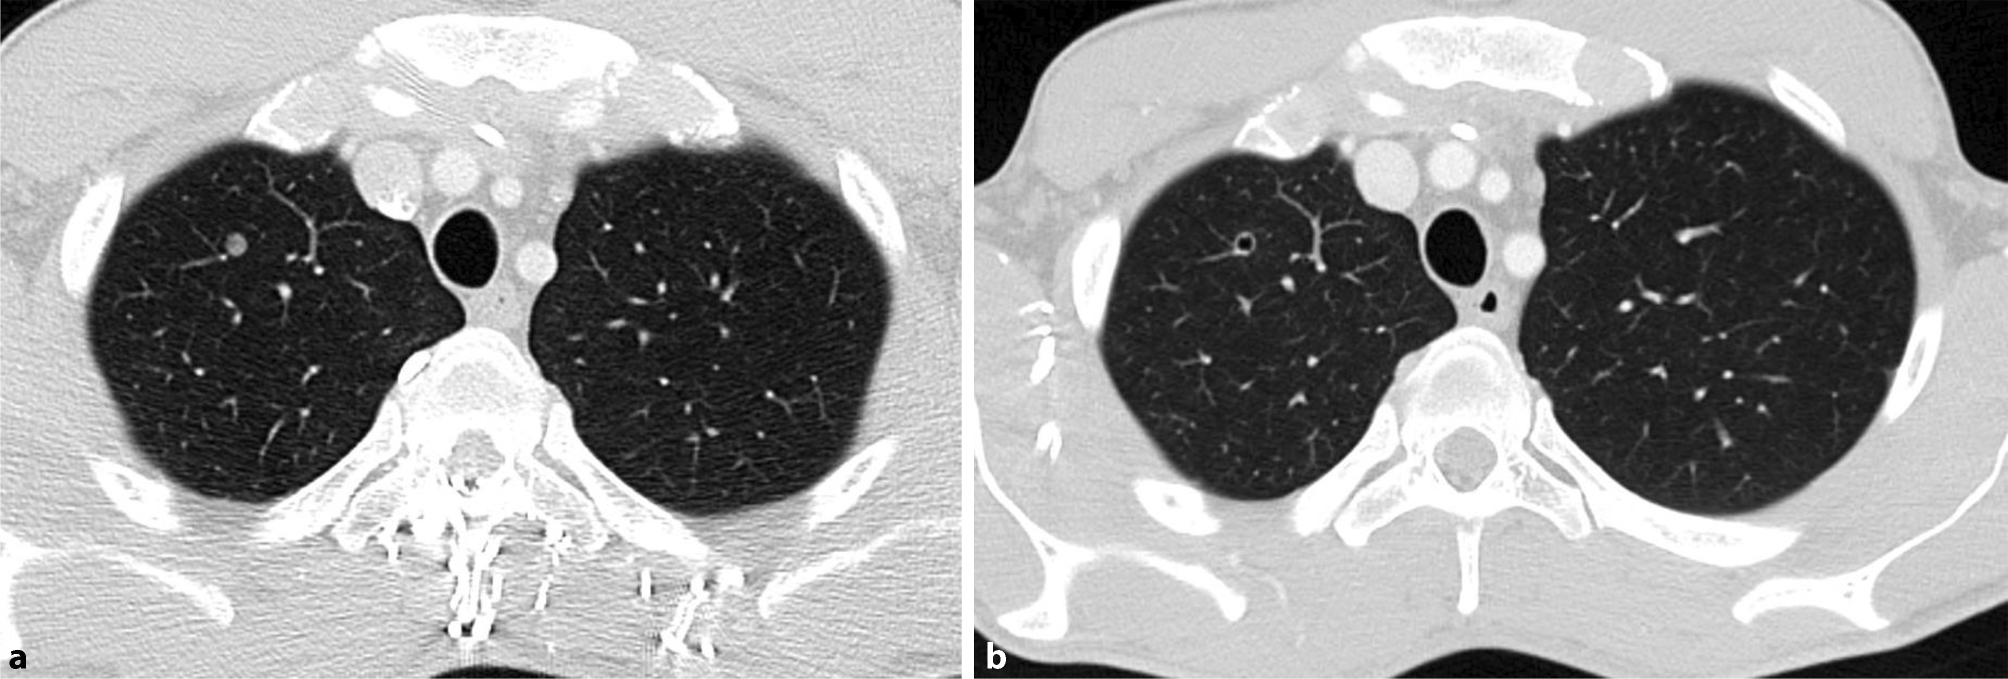

Fig. 2

Pulmonary metastasis: a March 2017, b June 2017

The patient received six cycles of palliative chemotherapy with docetaxel, cisplatin, 5‑fluorouracil (DCF) from June 2016 to October 2016 in a local hospital in Vienna. Although a partial response was seen after three cycles, the final CT scan exhibited progressive disease. Consequently, the hospital changed the treatment to pembrolizumab, which was given for three cycles every 3 weeks with a dose of 200 mg until January 2017. A subsequent restaging CT showed progressive disease; therefore, pembrolizumab was discontinued and no alternative treatment was given. Five months after discontinuation of the pembrolizumab treatment (June 2017), a new staging CT showed significant shrinkage of the metastases in Virchow’s triad (Fig. 1a, b), lung (Fig. 2a, b), liver (not shown), and lymph nodes (not shown). This spontaneous regression was remarkable, since the patient did not receive any treatment during this period.